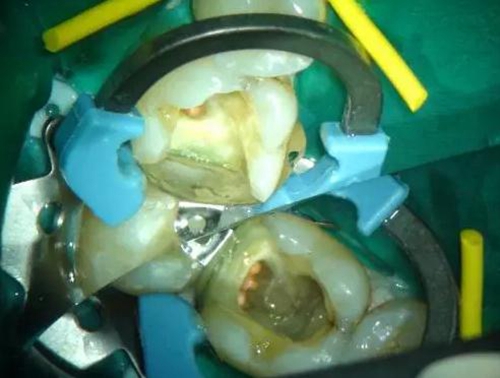

圖1 磨牙根管治療后進(jìn)行核修復(fù)。Palodent V3節(jié)段型成型片、分牙器及楔子均已就位。成型片不會(huì)受到橡皮障的影響??梢钥吹竭h(yuǎn)中洞型底部成型片的良好貼合。窩洞已酸蝕及涂布粘接劑,牙面呈“潮濕”狀態(tài)。使用橡皮障更利于術(shù)區(qū)濕度控制。然后向窩洞注射SDR。要注意避免:粘接劑在根管口堆積。SDR注射針頭可以探入根管口。雖然SDR的固化深度是4mm,但是建議現(xiàn)在根管口及髓底涂布薄層SDR并固化。此處位置太深,光固化燈可能光強(qiáng)不夠。然后再疊加SDR,直至低于洞緣2-3mm。